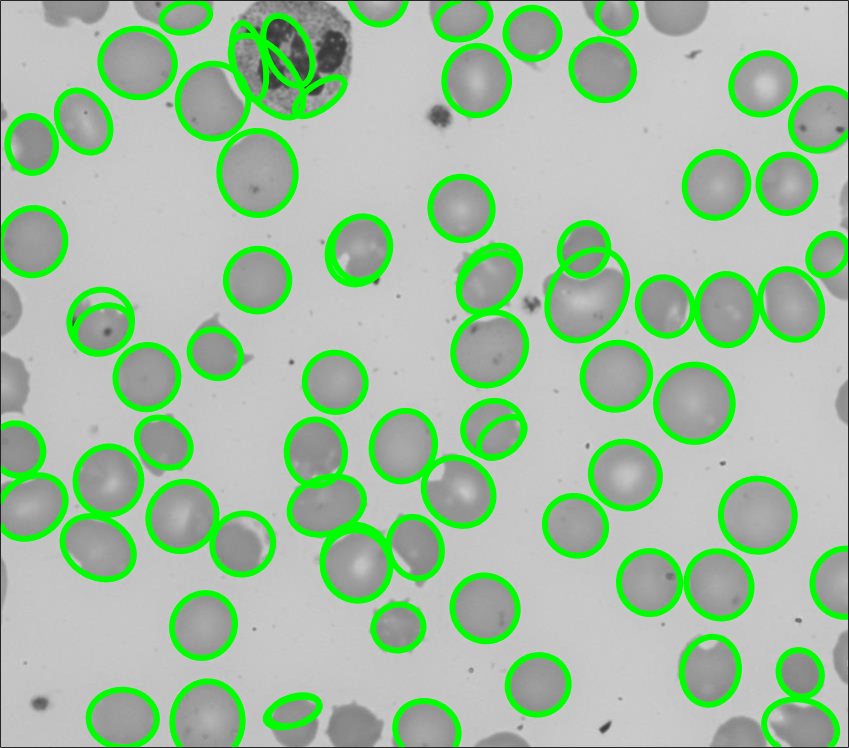

4.1.7 Application on Cell Counting

Finally, BayFit is deployed for cell counting in microscopy images, where multiple ellipse fittings are required. We conduct tests on both fluorescence and blood cell modalities, as depicted in Figs. 14 and 15, respectively. The used fluorescence images are collected by [52], while the blood cell images are sourced from the American Society of Hematology (ASH) image bank [53]. BayFit is applied to the edge maps of these images and returns ellipses one by one. In the bottom row of Fig. 14, BayFit not only delivers satisfactory approximations to various cell shapes but also provides highly accurate counts of the cell quantities. Even in challenging environments with a large number of irregular and small cells (Fig. 15), BayFit still demonstrates its potential in automating the labor-intensive task of cell counting. It is noticeable that our ellipse fitting approach in this context is a general-purpose algorithm that does not resort to additional application-related information or post-verification, such as shape or appearance constraints, which may further facilitate the performance. Other two applications including 3D reconstruction and elliptical object approximation are presented in Section 12.1 of the Supplementary Material.